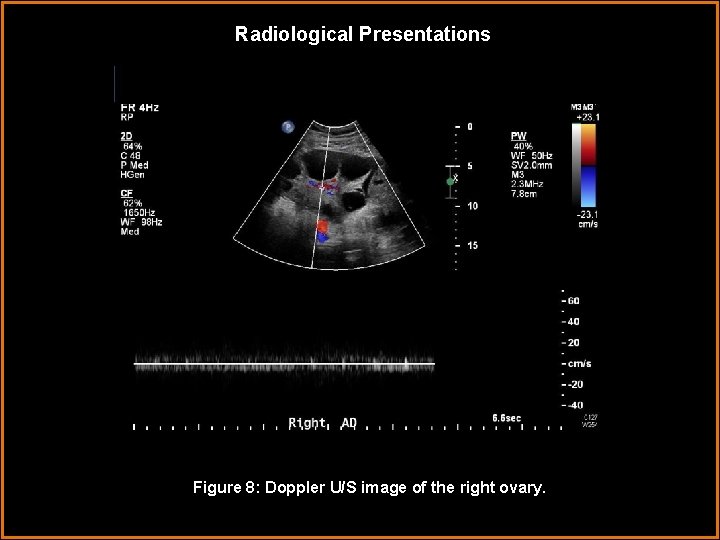

Radiological Presentations Figure 8: Doppler U/S image of the right ovary.

Findings and Differentials Findings: - Abdominal U/S images demonstrate moderate to large amount of ascites. The images of the right and left upper quadrants also show bilateral pleural effusions. - Transabdominal images of the pelvis also show ascites. The endometrium is diffusely echogenic and thickened to over 2 cm, consistent with a secretory phase appearance. - The ovaries are both grossly enlarged, containing multiple large peripheral anechoic areas with thin walls, consistent with simple cysts. The right ovary measures 14. 6 x 9. 7 x 12. 8 cm and the left ovary measures 11. 3 x 11. 9 x 12. 1 cm. The ovarian stroma is normal in echogenicity with flow demonstrated on Doppler bilaterally.

Discussion Ovarian torsion must always be considered in a patient with enlarged ovaries and pelvic pain. Torsion occurs when an ovary twists on its vascular pedicle and becomes ischemic. The torsed ovary will be enlarged, with a heterogeneous stromal echotexture secondary to edema, hemorrhage, and or necrosis. Evaluation of flow to the ovary is of limited value as flow may be detected in a torsed ovary and no flow may be detected in a normal ovary. In cases of torsion, the edematous stroma pushes the normal follicles peripherally, creating an appearance of peripheral cysts similar to that seen in PCO and OHSS. In this patient’s case, flow is demonstrated, and torsion is unlikely because the visualized ovarian stroma has a homogenous echotexture and normal echogenicity. 4 Of course torsion and OHSS can coexist and it cannot be overemphasized that torsion should be considered in every case of OHSS that presents with pelvic pain.